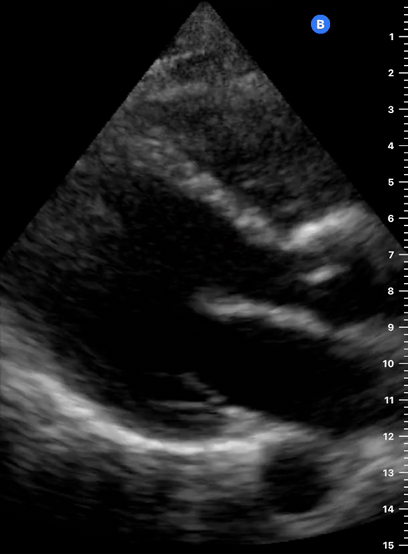

SX

SUBXIPHOID VIEW

This is the standard window taught in FAST and might be the only one available during cardiopulmonary resuscitation (CPR). This view uses the liver as an acoustic window. To obtain good visualization is essential to handle the probe almost parallel to the anterior abdominal wall, trying to place it under the xiphoid process, pointing to the left shoulder. A deep inspiration or half inspiration can be useful to bring the heart closer to the probe and improve visualisation.

Remember that in the cardiac preset, the screen marking is on the right side. As a result, and unlike the FAST exam, the probe marking points towards the patient’s left. This view is used mainly to look for pericardial fluid, but it also provides information about ventricle size, chamber relationship and valvular abnormalities.